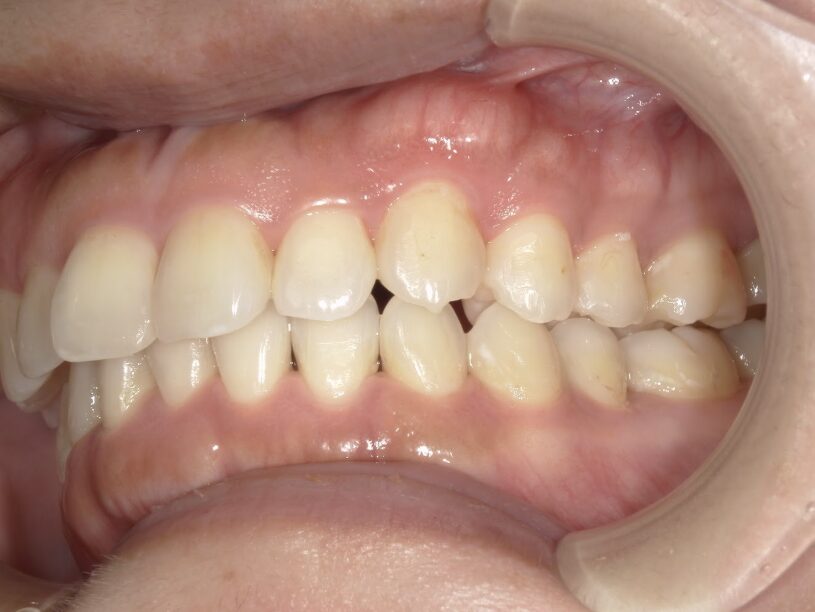

過蓋咬合

治療前

ガタガタを主訴に当院を受診され、上下前歯部に叢生(ガタガタ)と過蓋咬合(上の歯が下の歯を深く覆いかぶさっている状態)を認めました。